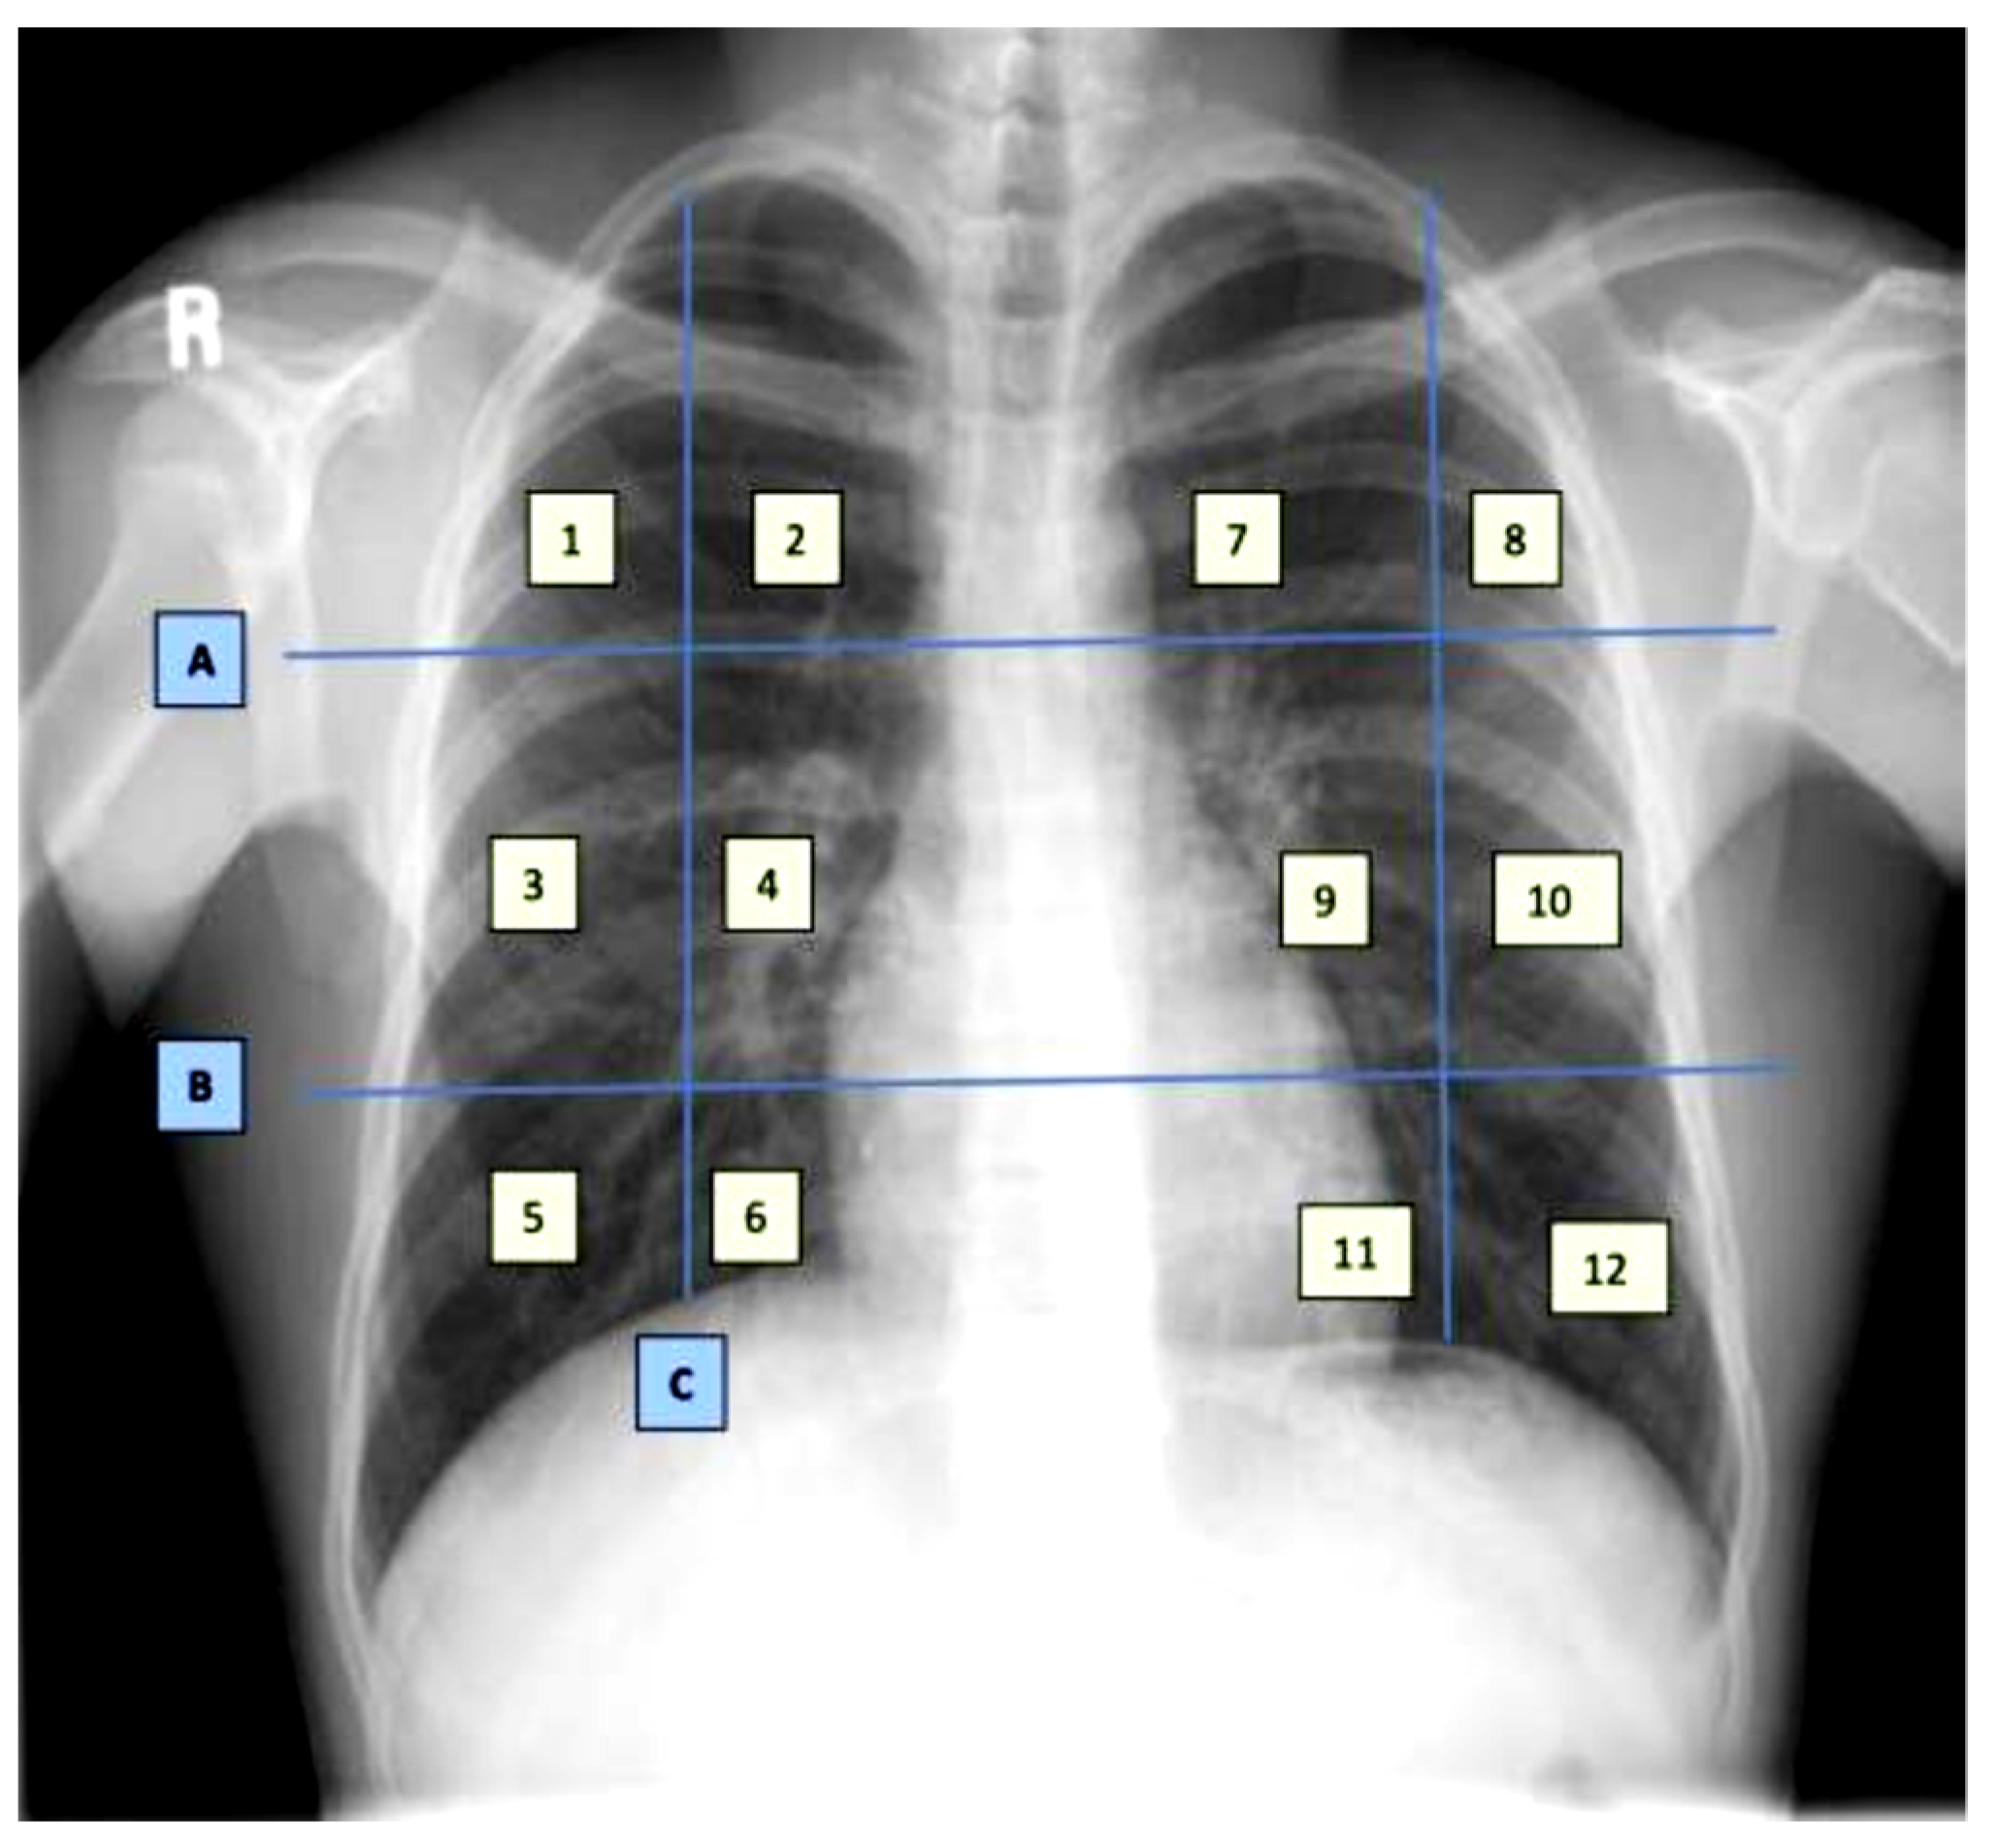

The dataset contains demographic features (gender, age), laboratory results from complete blood count CBC (hematocrit, hemoglobin, mean corpuscular hemoglobin concentration (MCHC), mean corpuscular hemoglobin (MCH), mean corpuscular volume (MCV), mean platelet volume (MPV), red blood cells (RBC), Platelet count, red cell distribution width (RDW), white blood cells (WBC), and radiological findings and comorbidity (cancer, coronary artery disease (CAD), hypertension (HTN), asthma, chronic obstructive pulmonary disease (COPD), type II diabetes mellitus (T2D), liver cirrhosis (LC), chronic hepatitis B (CHB), chronic hepatitis C (HCV) and chronic kidney disease (CKD)). Age and all CBC attributes are numeric, while the remaining attributes are categorical. The CXRs are annotated in twelve zones, as shown in Figure 1. Initially the CXR is divided in two upper (A) and lower zone (B) and also the junction (C). Then these zones are further divided into twelve zones which indicate the points where the radiologist assign severity levels. The zone attributes consist of three possible values (0–2) indicating the severity of ground glass opacity (GGO). Zero indicates the absence of GGO. Ultimately, the dataset contains 35 predictors and 2 class attributes.

Figure 1. Chest X-ray zone segmentation and annotation [17].